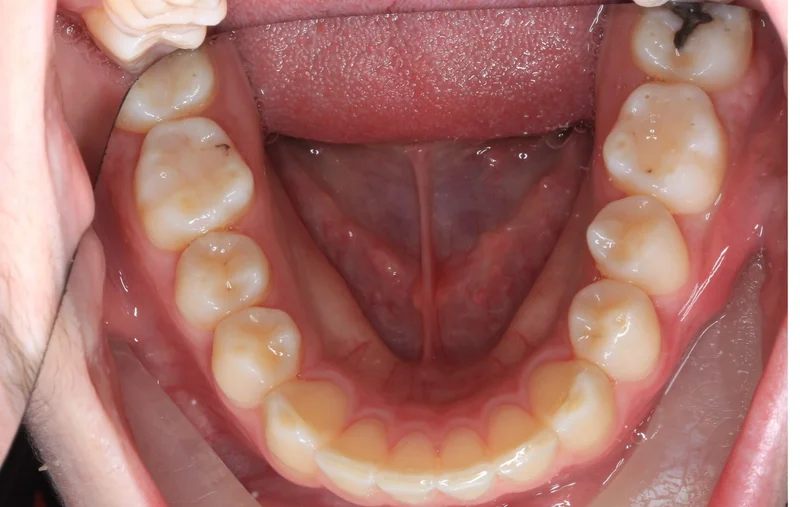

Lower Arch

Lower Arch - Before Treatment

Before

Lower Arch - After Treatment

After